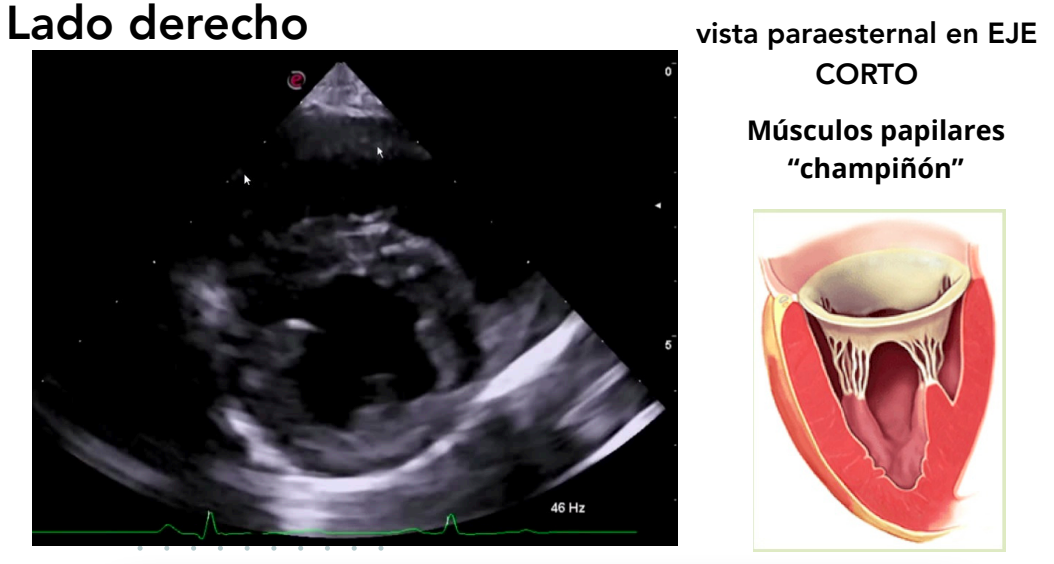

Vista paraesternal en eje corto

- Niveles observables:

- Músculos papilares ("champiñón")

- Válvula mitral ("boca de pez")

- Base cardíaca

- Tracto de salida del ventrículo derecho